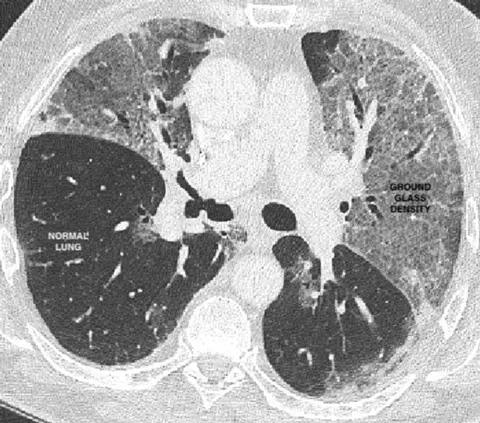

Healthy lungs should look black on a scan because they are mostly air, but with Covid they often have what's known as a "ground glass" appearance - like opaque windows in a bathroom.

UCLThere is an obvious problem here. Other respiratory diseases can also cause this shadowy appearance, and so it may be hard to distinguish between Covid-19 and seasonal flu.